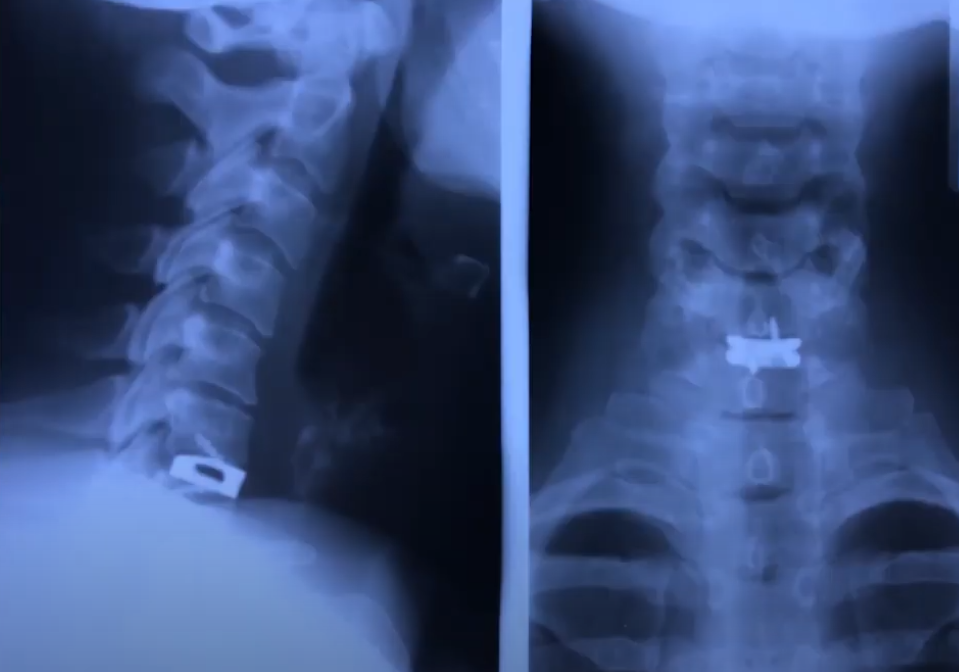

Пациенту проводили стандартную операцию с передним доступом, установили швейцарский Кейдж с двумя винтами, выполнили стабилизацию. Швейцарский Кейдж имеет нулевой профиль, поэтому контакта в сосудами нет.